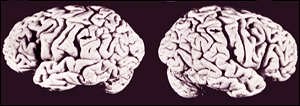

Einstein's brain found to be anatomically distinct

Einstein allowed his brain to be studied after his death

We always thought something must have made Albert Einstein smarter than the rest of us. Now, scientists have found that one part of his brain was indeed physically extraordinary.

In the only study ever conducted of the overall anatomy of Einstein's brain, scientists at McMaster University in Ontario, Canada, discovered that the part of the brain thought to be related to mathematical reasoning - the inferior parietal region - was 15 percent wider on both sides than normal.

Furthermore, they found that the groove that normally runs from the front of the brain to the back did not extend all the way in Einstein's case. That finding could have applications even to those with more pedestrian levels of intelligence.

"That kind of shape was not observed in any one of our brains and is not depicted in any atlas of the human brain," said Sandra Witelson, a neuroscientist who led the study, published in this week's issue of The Lancet, a British medical journal.

"But it shouldn't be seen as anatomy is destiny," she added. "We also know that environment has a very important role to play in learning and brain development. But what this is telling us is that environment isn't the only factor."

The findings may point to the importance of the inferior parietal region, Witelson said.

While the differences may be extraordinary between Einstein and everyone else, there may be more subtle, even microscopic, differences when the anatomies of the brains of people who don't fall into the genius category are compared with each other, she said.

The researchers compared the founder of the theory of relativity's brain with the preserved brains of 35 men and 56 women known to have normal intelligence when they died.

With the men's brains, they conducted two separate comparisons - first between Einstein's brain and all the men, and next between his brain and those of the eight men who were similar in age to Einstein when they died.

They found that, overall, Einstein's brain was the same weight and had the same measurements from front to back as all the other men, which Witelson said confirms the belief of many scientists that focusing on overall brain size as an indicator of intelligence is not the way to go.

Witelson theorized that the partial absence of the groove in Einstein's brain may be the key, because it might have allowed more neurons in this area to establish connections between each other and work together more easily.

She said it is likely that the groove, known as the sulcus, was always absent in that part of Einstein's brain, rather than shrinking away as a result of his intelligence, because, as one of the two or three landmarks in the human brain, it appears very early in life.

"We don't know if every brilliant physicist and mathematician will have this same anatomy," Witelson said. "It fits and it makes a compelling story, but it requires further proof."

John Gabrieli, an associate professor of psychology at Stanford University who was not connected with the study, said the finding relating to the groove and connections between the neurons in the brain may be the key.

"We don't have a clue, so anything that is suggested is interesting," he said. "There must have been something about his brain that made him so brilliant."

Brilliance of the kind Einstein possessed is so extreme, however, that although the findings may give a clue to the neurology of genius, whether they could apply to normal differences in intelligence is more doubtful, Gabrieli said.

Witelson said the next stage is to scan the brains of living mathematicians and look for minute differences.

Witelson and her team acquired Einstein's brain after they were contacted by its keeper, scientist John Harvey, who had read about the university's brain research.

Harvey was a pathologist working at a small hospital in Princeton, N.J., when Einstein died in 1955 at the age of 76. Harvey performed the autopsy, determined Einstein died of natural causes and took the brain home with him.

Some parts of the brain were given to scientists, but no major study was ever conducted, until now.